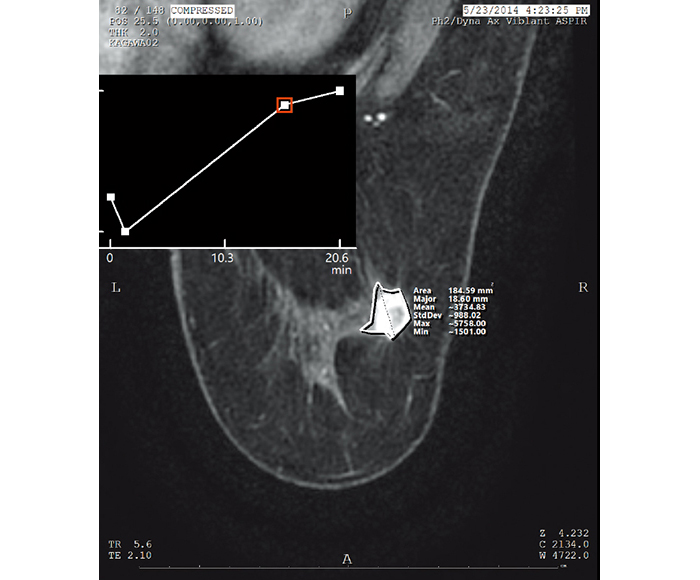

Values for ROI and X-ray gauging can be obtained from the information in each imaging modality.

![[image] ROI (Region of interest) X-ray](https://asset.fujifilm.com/www/ar/files/2025-07/046bfe4bfc03d6ebc9e27f55b5106b78/pic_amulet-bellus-2_05.jpg)

ROI (Region of interest)

![[image] Time intensity curve X-rays](https://asset.fujifilm.com/www/ar/files/2025-07/3f4b2c212d2a9ccf77989eac7a2e1f6d/pic_amulet-bellus-2_06.jpg)

Time intensity curve